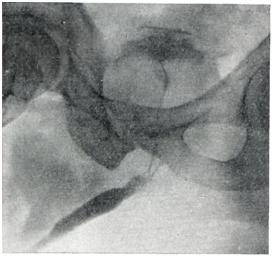

Рис. 4.

Внутрипузырная аденома предстательной железы (лакунарная цистограмма).

Применяют экскреторную урографию, цистографию и уретроцистографию; наиболее рациональна лакунарная уретроцистограмма по Кнайзе и Шоберу (рис. 4). Кислород, введенный по катетеру в количестве 150—200 мл, растягивает мочевой пузырь в виде купола. Введенное вслед за кислородом жидкое контрастное вещество (20% раствор сергозина в количестве 20 мл) располагается в области дна мочевого пузыря, выявляя внутрипузырный рост аденомы предстательной железы. Этим методом определяют ряд типичных рентгенологических симптомов: «берета» (рис. 5), удлинения мочеиспускательного канала (рис. 6), «клинка сабли» (рис. 7), приподнятого дна.